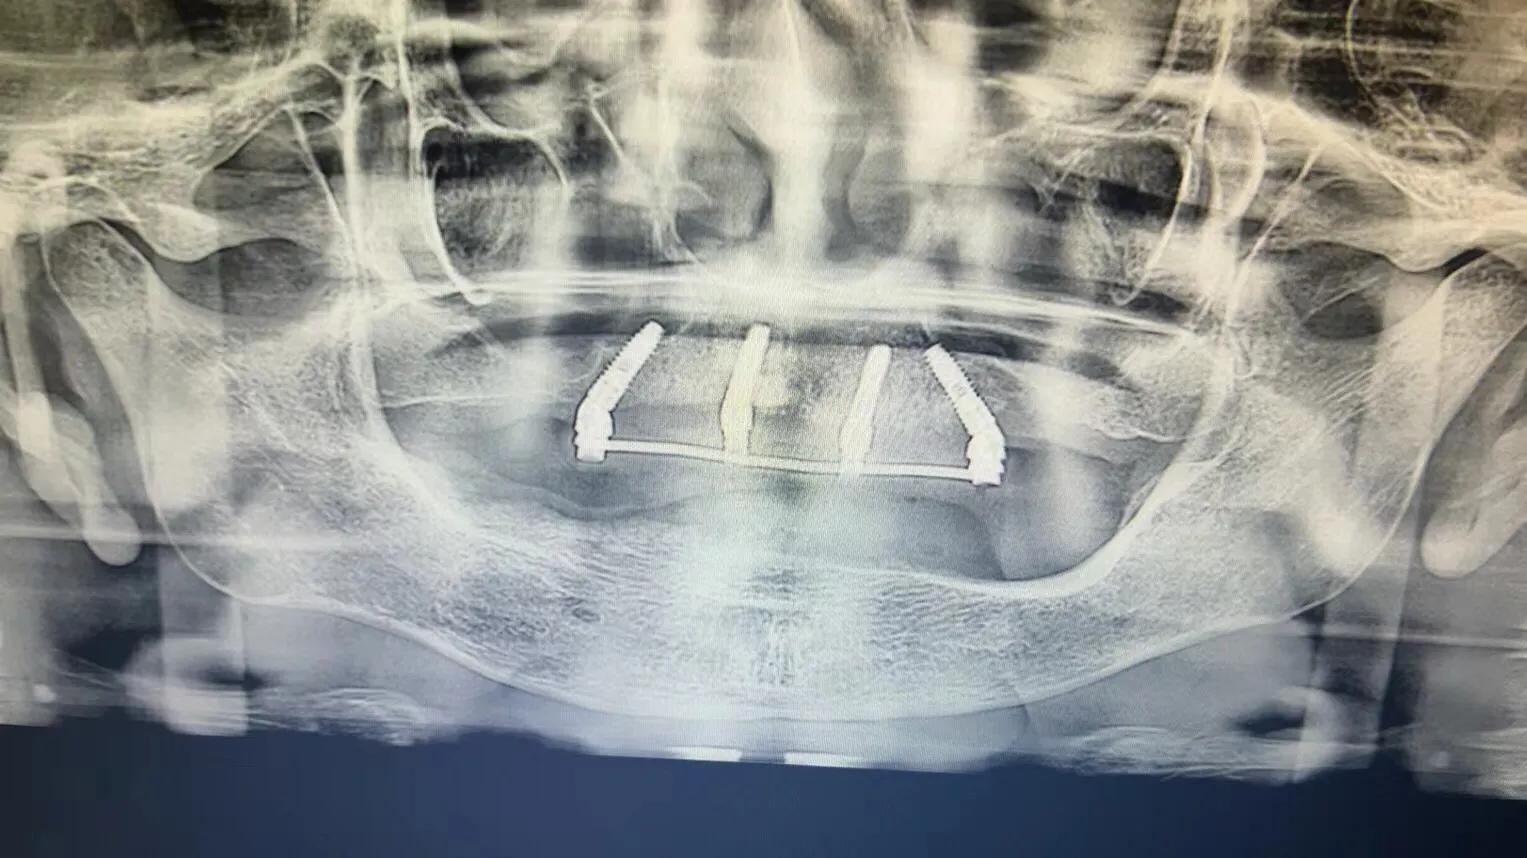

典型的負(fù)重,All-On-4。

這就是傳說(shuō)中的當(dāng)天戴牙當(dāng)天吃飯,網(wǎng)上到處宣傳的就是這種種植方法。但是不是每一個(gè)人都能做這個(gè),All-on-4一般需要預(yù)約,醫(yī)生種植完畢,技師馬上開(kāi)始取模做牙,大概5小時(shí)左右就可以戴上臨時(shí)牙回家吃飯了,休息一兩天,正常吃飯是沒(méi)問(wèn)題的。

1. 問(wèn)題是比較貴,但是現(xiàn)在價(jià)格也越來(lái)越低了,韓國(guó)種植體半口5萬(wàn)多到8萬(wàn)就可以做。歐美的植體半口還是要10萬(wàn)以上,諾貝爾半口得20萬(wàn)以上。

2. 還有一個(gè)問(wèn)題就是骨件,不是每個(gè)人都可以做。骨頭太差,只能做常規(guī)的種植,等3-6個(gè)月戴牙,可能更久,中間只能用臨時(shí)牙過(guò)度。負(fù)重開(kāi)始戴的也是臨時(shí)牙,但是這個(gè)臨時(shí)牙和常規(guī)島臨時(shí)牙不一樣,咬合力挺好

3. 有些患者以為一顆牙也可以這樣,一顆是不行的,至少連續(xù)4顆才可以,比如門牙連續(xù)4顆就可以做。